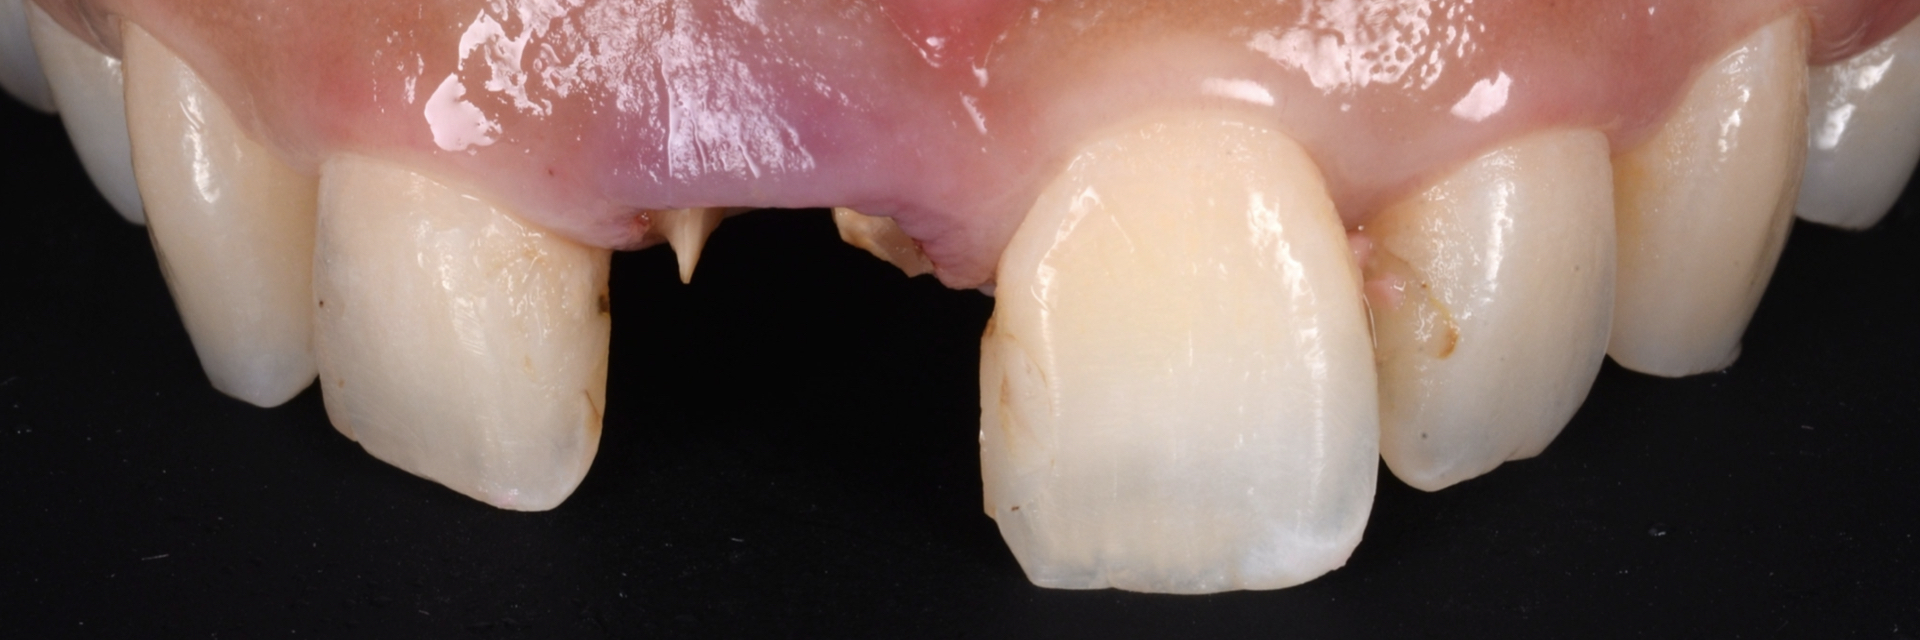

治療後

| 治療内容 | 5前歯をジルコニアベースのセラミッククラウンに置き換えました。 |